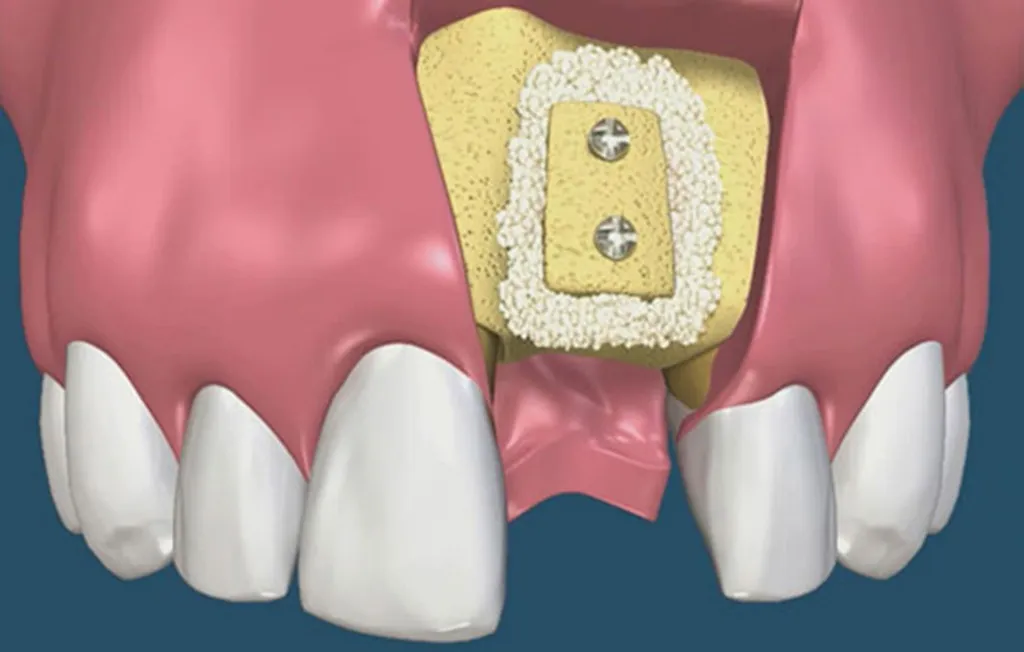

Hiện nay, kỹ thuật cấy ghép implant là phương pháp nha khoa phổ biến nhất. Tuy nhiên, để thực hiện được việc cấy ghép an toàn thì